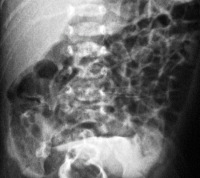

Инструментальные методы диагностики включают в себя УЗ-исследование, рентгенографию органов брюшной полости, при необходимости - компьютерную и магнитно-резонансную томографию. Картина УЗИ в зависимости от формы мекониального перитонита может содержать локальные или диффузные участки обызвествления, гиперэхогенные образования с четким контуром (псевдокисты), расширение петель кишечника, экссудат в брюшной полости. Рентгенограмма и томограммы подтверждают аналогичные нарушения. Кроме того, еще в пренатальном периоде может проводиться кордоцентез для идентификации аномалий строения ДНК, муковисцидоза или TORCH-инфекций.